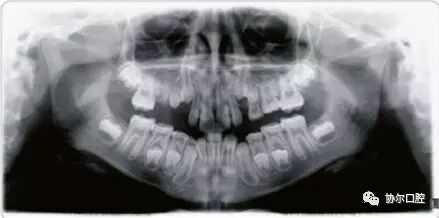

CRANEX D

卡瓦牙科数字全景机

CRANEX D 可进行标准成人全景摄影,小儿全景摄影,区域全景摄影,TMJ摄影,鼻副窦摄影和头颅定位摄影。将前牙扫描层厚增加50%,提高前牙区图像质量,并使病人定位简便。

成人全景摄影:

所有全景摄影程序均采用自动颈椎补偿,减少前牙区重叠伪影,使前牙区结构显示更加清晰

小儿全景摄影:

缩短摄影时间,减少摄影区域,降低病人曝光剂量

TMJ摄影:

TMJ(颞下颌关节)摄影可进行开口位或闭口位检查,用于观察关节的解剖结构。

区域全景摄影:

将标准全景摄影区域分为1到5个区域,任意组合后进行摄影,降低病人曝射剂量。

头颅定位摄影:

可进行头颅侧位和后前位摄影

我们标配进KaVo3D eXam i加这台KaVo CRANEX D数字化全景机,虽然设备成本高N倍,但为了协尔众多忠粉们也值得。